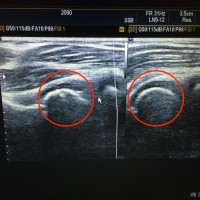

野球肘予防法その2

おはようございます。 四ツ谷接骨院の藤本です。 本日は、野球肘予防法その2 と題しましてお話させていただきたいと思います。 痛みの出ない初期の離断性骨軟骨炎をどのように 悪化しないように予防す …